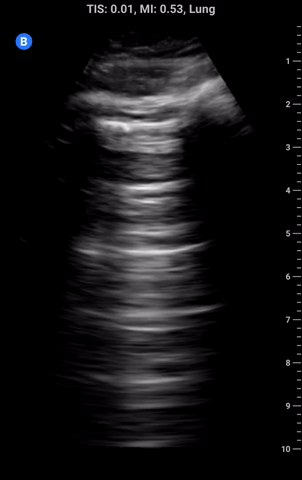

M-Mode and Pleural Sliding: In addition to B-mode imaging, M-mode can be used to assess for the presence of pleural sliding and lung pulse. In the image above on the left we see M-mode being used on a shallow lung view with the pleural line highlighted in red. Note the static soft-tissue/intercostal muscles above the line create layers of horizontal lines whereas BELOW the pleural line there is a scattered random pixel pattern. This is due to the motion of the intact pleural interface and the scatter from the lung parenchyma colloquially referred to as “sea shore” sign where the lung is the sand and the soft tissue the water. Even if the lung is not moving there should still be movement of the pleura from the heart/aorta creating a lung pulse which can be seen below the blue arrows.